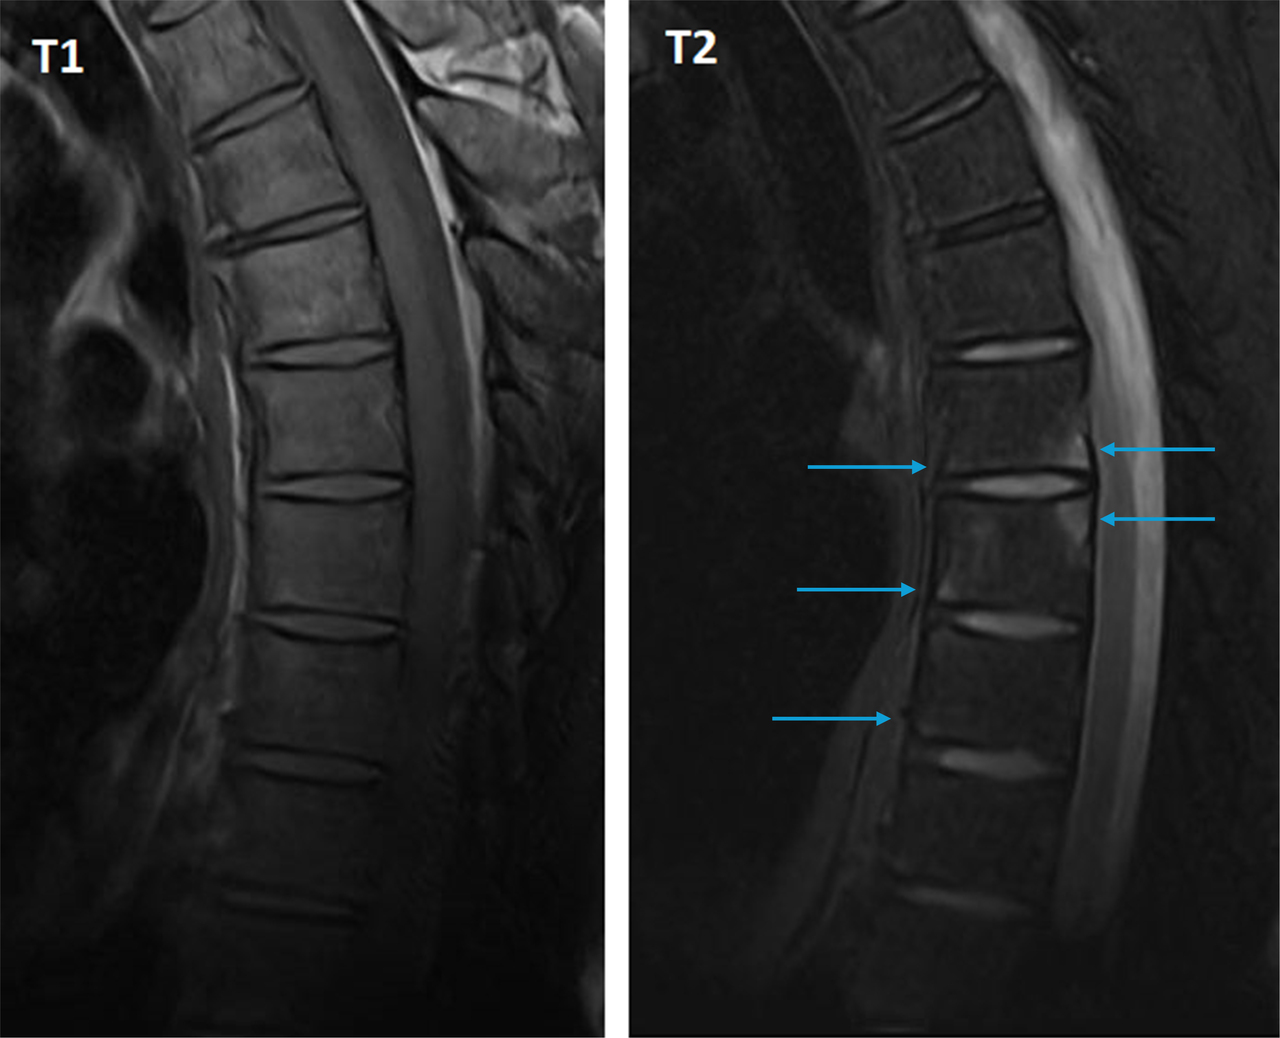

Voici des IRM en séquences T1 et T2 avec suppression du signal de la graisse (Dixon water) :

Figure 2 (Salomé Abdellaoui, La Revue du Praticien)

La vertèbre T6 montre deux coins inflammatoires : antéro-inférieur et postéro-supérieur.

L’IRM rachidienne montre de nombreux coins inflammatoires en hypersignal T2, qui témoignent d’une atteinte enthésitique au rachis. On les distingue des coins « graisseux » qui apparaissent en hypersignal T1 et en hypersignal T2 ou iso-signal sur les séquences avec suppression du signal de la graisse.

Figure 3 (Salomé Abdellaoui, La Revue du Praticien)